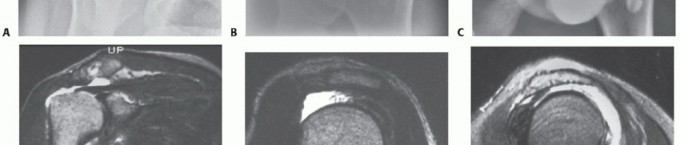

FIG 1 • A,B. Type III acromion, the so-called hooked acromion, on the outlet and AP views. C. Arthrogram confirming the presence of a rotator cuff tear with dye in the glenohumeral joint and the subacromial bursa simultaneously. D. T2-weighted coronal MRI showing cuff tear and its lateral to medial extent. E. T2-weighted sagittal oblique MRI showing the AP extent of the cuff defect. F. Another T2 sagittal oblique MRI showing the tear involving the teres minor but not the subscapularis. G. Axial T2 MRI of the same tear showing rupture of the teres minor with an intact subscapularis.

Standard radiographs, including anteroposterior (AP) views in internal and external rotation, an axillary view,

and an outlet view, should always be taken to look for the type of acromion (

FIG 1A

), acromioclavicular joint changes, and narrowing of the acromial-humeral interval (

FIG 1B

) and to rule out other conditions.

Additional preoperative studies include MRI, ultrasound, or arthrography.

Arthrography once was the gold standard but now is used only under rare circumstances (ie, when an MRI cannot be done). It can show a full-thickness cuff tear (

FIG 1C

) but requires an intra-articular injection with fluoroscopy and radiography.

The most commonly used study is an MRI. It not only shows the integrity of the tendons but also provides a three-dimensional view of the cuff (

FIG 1D-G

). This capacity makes the MRI a versatile preoperative planning tool.